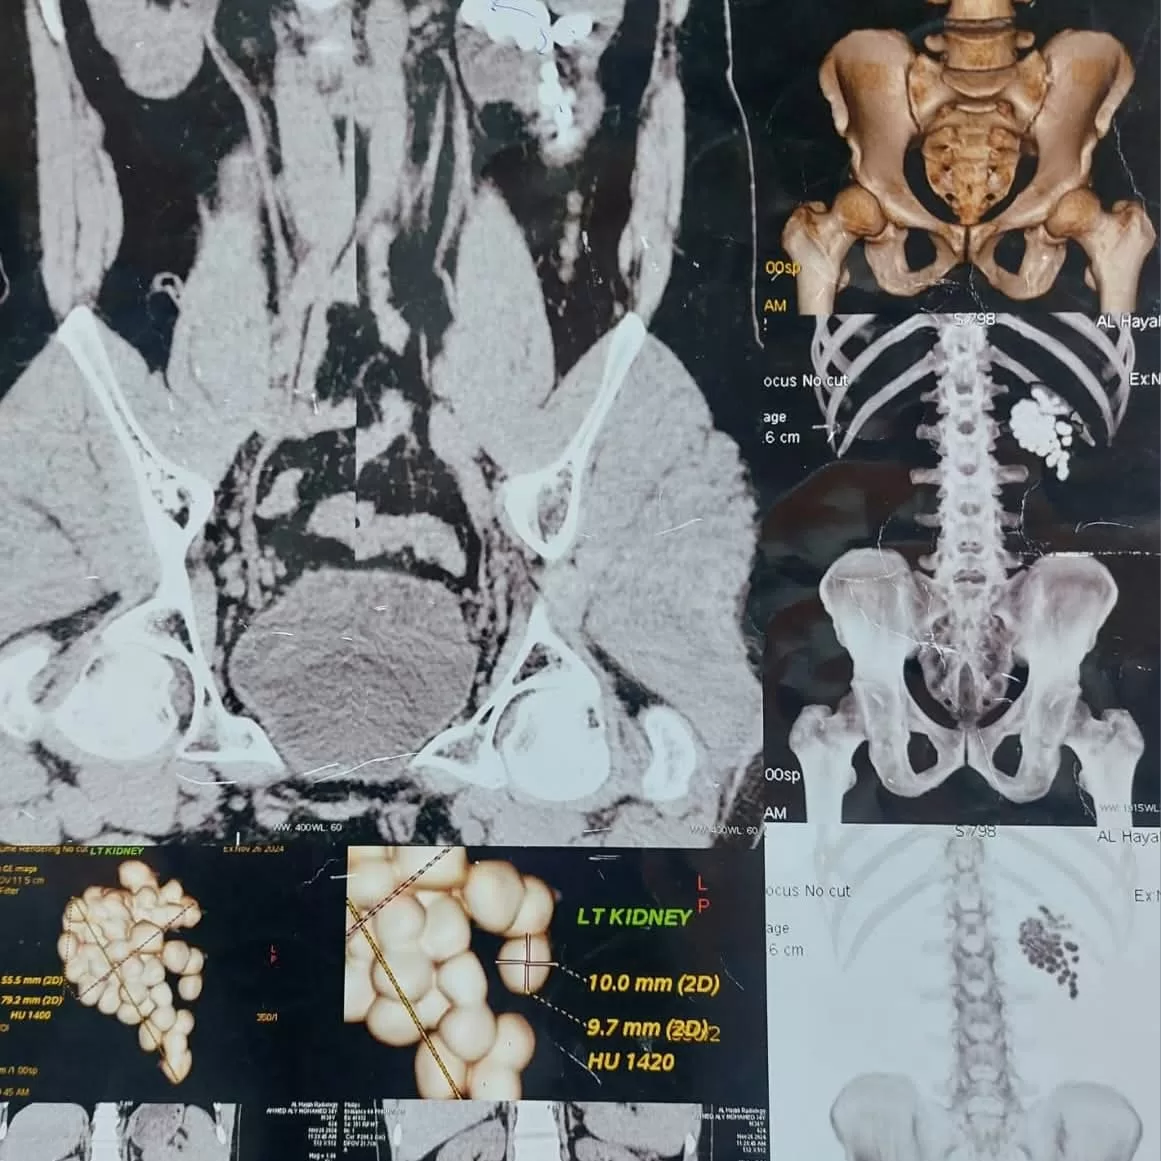

وأوضح الدكتور مصطفى عبد الرازق، رئيس قسم جراحة المسالك البولية، أن المريض وصل إلى المستشفى وهو يعاني من آلام متكررة وارتفاع في نسبة الأملاح، وبالفحوصات تبين وجود عدد كبير من الحصوات المتجمعة في حوض الكلية اليسرى مما استدعى تدخلاً جراحيًا عاجلًا للحفاظ على سلامة الكلية. وتم تجهيز المريض للعملية وإجراء التخدير العام، ليبدأ الفريق الطبي استخدام تقنية منظار الكلى عن طريق الجلد، والتي تُعد من أحدث الأساليب لإزالة الحصوات الكبيرة والمتعددة دون الحاجة إلى فتح جراحي.

وأضاف أن العملية استغرقت نحو ساعتين، جرى خلالها استخراج جميع الحصوات بعد تفتيتها باستخدام تقنيات التفتيت الهوائي والليزر بحسب طبيعة كل حصوة، كما جرى تنظيف حوض الكلية بالكامل ووضع أنبوب تصريف مؤقت لضمان خروج السوائل بشكل آمن. وخرج المريض من غرفة العمليات في حالة مستقرة، مع متابعة دقيقة لوظائف الكلى داخل وحدة الإفاقة، حيث أظهرت المؤشرات الطبية تحسنًا ملحوظًا.